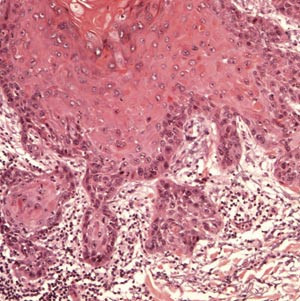

Aktinisk keratose har forskjellige presentasjonsformer. Lesjonen er begrenset til epidermis og gjenkjennes ved tap av cellenes polaritet, cytologisk atypi og enkelte mitoser (e-fig 1, fig 2, fig 3). De atypiske keratinocyttene finnes oftest nær basallaget (e-fig 1), men atypiske epitelceller kan også finnes i andre lag av epidermis når lesjonen progredierer (fig 2, fig 3). På overflaten er de atypiske keratinocyttene dekket av hyperkeratose og parakeratose, noe som gjør at epidermis blir fortykket når lesjonen blir mer avansert.

Grensen mellom dysplastiske og normale keratinocytter er ofte skarp. De atypiske keratinocyttene danner ofte tappformede nedvekster fra basallaget som kan gå over i svettekjertler og hårfollikler uten gjennomvekst av basalmembranen. De vanligste formene er atrofisk, hypertrofisk, bowenoid og lichenoid. Den atrofiske varianten har ofte lettere atypi, mens den hypertrofiske og den bowenoide er karakterisert ved grov atypi og manglende polaritet i hele epitelet, som ved cancer in situ. Bare manglende infiltrasjon gjennom basalmembranen skiller hypertrofisk og bowenoid form fra plateepitelkarsinom (fig 4).